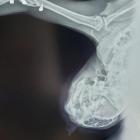

Śnieżek, jak określa „Pan Kot”, to osiedlowy pupilek, mieszkający właśnie na ulicy Białowieskiej. Z powodu kulejącej łapki został przyjęty na diagnostykę i przy okazji kastrację. W gabinecie weterynaryjnym okazał się jednak, że kot został postrzelony – badanie rentgenowskie wykazało śrut w dwóch miejscach – w udzie i łokciu. Śrut został usunięty, ale łapka nie będzie już sprawna.